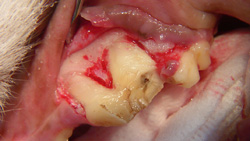

The buccal alveolar bone is removed using a round ball bur (#2, surgical length, friction grip) in a water-cooled, high-speed handpiece. The amount removed will depend on the experience and skill of the operator, but removing the alveolar bone to expose 25% to 50% of the buccal root surface should suffice. The removal of alveolar bone is guided by palpation and visualization of the alveolar juga of each root.